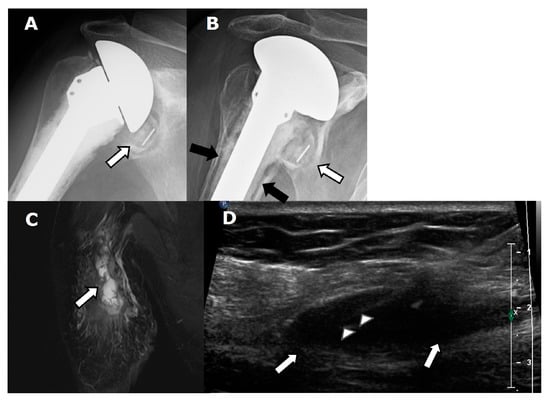

4.2.1. Loosening and Hardware Dissociation

4.2.2. Stress Shielding and Fractures

4.2.3. Periprosthetic Joint Infection (PJI)

4.2.4. Rotator Cuff Tendon Tears